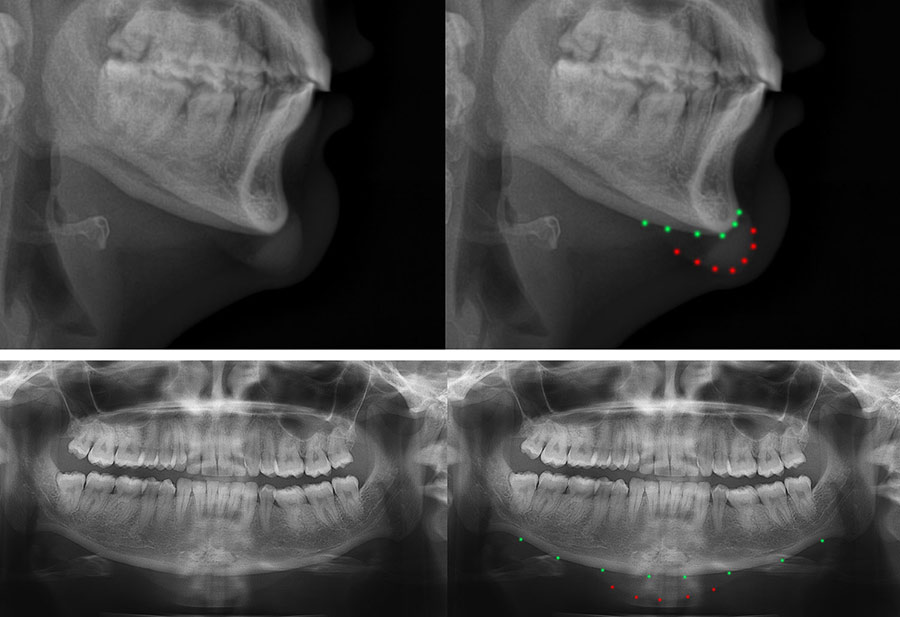

• The images on the left are taken a patient who had chin implant surgery in Eastern Europe. Dr De Silva performed revision chin implant surgery to remove the unsuitable implant and insert a tailor-made implant that gave a natural looking aesthetic.

• In this woman in her 20’s the implant that was inserted abroad was too large for the woman’s jawline, and moved after the surgery, resulting a box shaped chin. The green marks show the natural jawline and the red marks show the position of the chin implant that was inserted in Eastern Europe.

• On the before and after photos on the left, Dr De Silva removed the previous implant and inserted a high-grade silicone implant that was tailor-made to the patient’s jawline and facial shape. The implant was secured with two mini screws to maintain the position of the implant long-term.

• The left photograph shows the before appearance with a long and box-shaped chin and the right photograph shows the more feminine and heart-shaped appearance 1-week after surgery.